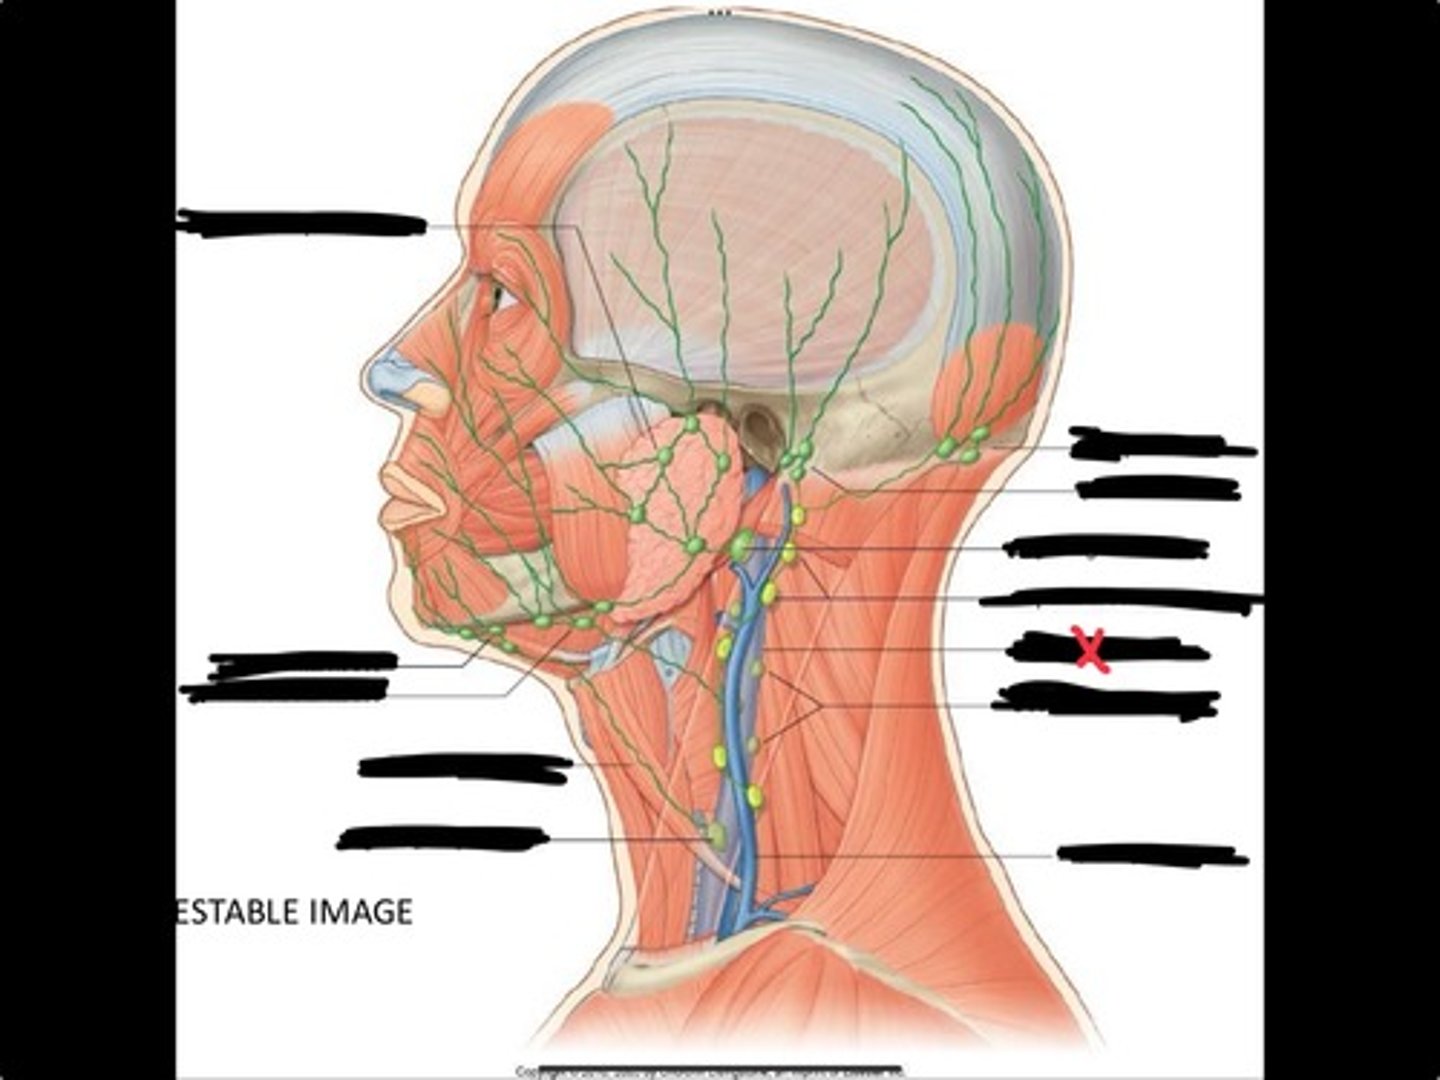

Jugulo-omohyoid node

Submandibular nodes

Submental nodes

Pre-articular/parotid nodes

Occipital nodes

Mastoid nodes

Jugulodigastric nodes

Superficial cervical nodes

Internal jugular vein

Deep cervical nodes

External jugular vein